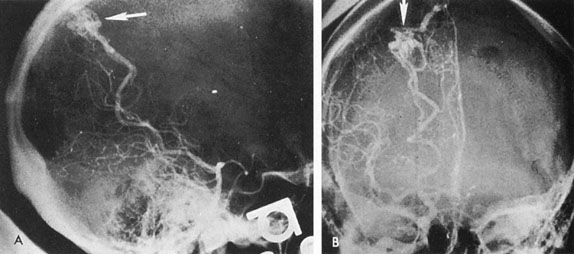

Of particular interest are those AVMs that involve the occipital lobe (Fig. 9). The clinical differentiation of migraine from a cerebral AVM was previously regarded as difficult because the clinical features of occipital lobe AVMs include visual phenomena or headaches. However, in most cases the clinical distinction is possible. In 26 cases with occipital AVM, two distinct syndromes were defined in 18 patients: occipital epilepsy and occipital apoplexy.73 Focal seizures with occipital malformations consist of elementary visual sensations similar to the phenomena evoked by direct cortical stimulations. When seizure activity occurs in the striate cortex (area 17), the patient usually reports sensations of moving lights in the right or left homonymous fields. The sensations are poorly formed, episodic, usually brief, sometimes colored, and unassociated with the angular, scintillating figures so characteristic of migrainous cortical phenomena. Epileptic discharges from areas 18 and 19 cause photopsias that are unlikely to remain stationary and to flicker rapidly. The epileptic photopsias usually last only seconds; occasionally they last for a few minutes before the onset of a generalized seizure. In other instances only the brief visual episodes occur without spreading to produce a generalized seizure. Momentary dimming or blindness in one or both homonymous fields may be experienced with seizure activity in the occipital areas.

Fig. 9. Carotid arteriogram of an occipital lobe arteriovenous malformation (AVM). Lateral (A) and frontal (B) projections demonstrating a small occipital AVM (arrow). The patient was a 23-year-old woman who presented with severe apoplectic unilateral headache, total left homonymous hemianopia, and mild nuchal rigidity. Despite xanthochromic cerebrospinal fluid, she was initially diagnosed elsewhere as having migraine. An AVM was successfully resected, and a small occipital lobe hematoma was removed.

Occipital apoplexy results from hemorrhage and hematoma formation within the occipital lobe and is characterized by sudden severe headache and homonymous visual field loss. Homonymous hemianopia is the most important sign produced by vascular malformations of the occipital lobe. Compression and necrosis of visual pathways by an intracerebral hematoma are the principal mechanisms. Usually the hematoma is large and tends to split or dissect longitudinally through the white matter of the occipital lobe. The effects of compression may be reversed by prompt, surgical evacuation of the hematoma.73 With hemorrhage into one occipital lobe, hemianopia in the visual field of the contralateral normal occipital lobe may develop, producing total blindness that can last for several days. The rapidly expanding hematoma may shift the damaged hemisphere anteriorly, or across the midline, with downward herniation of the uncus through the tentorial incisura. This shift compresses the posterior cerebral arteries and accounts for bilateral occipital lobe dysfunction. Arrest of function in the undamaged occipital lobe may be due to an interhemispheral inhibitory phenomenon termed diaschisis. Visual field defects with occipital AVMs are regularly due to hemorrhage and hematoma formation. Congenital arteriovenous malformations can occupy the entire occipital pole (the macular projection area) for decades without producing visual field defects.